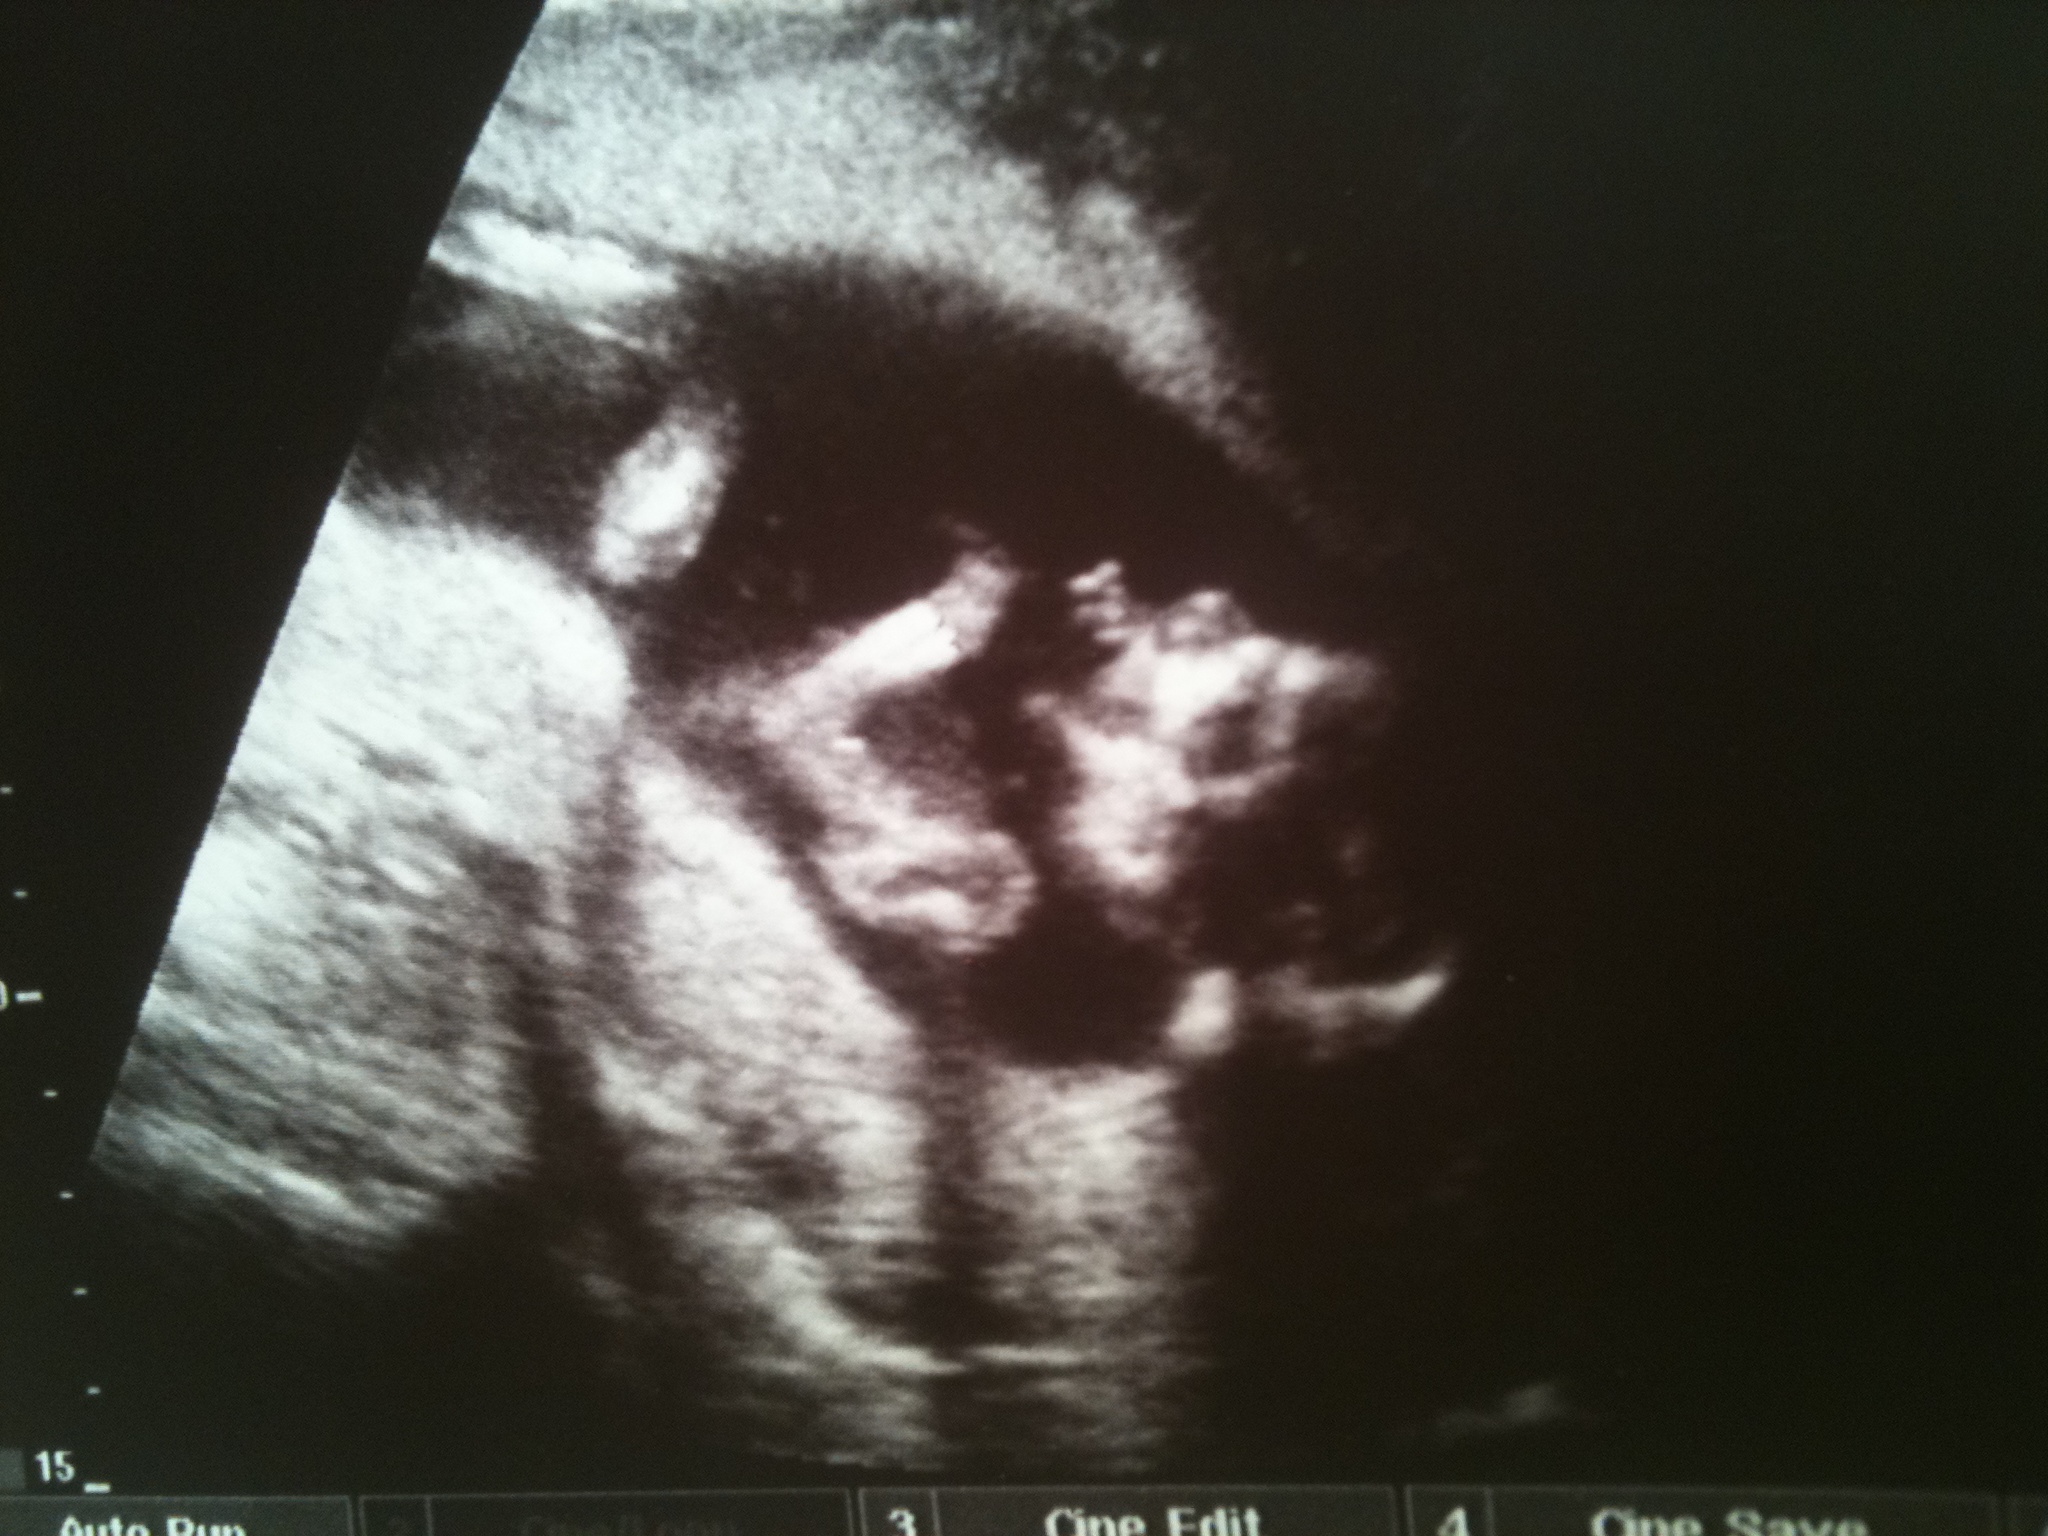

prajem vela zdravia

P.S.: Už aby si začal zháňať autosedačku, teraz sa ti kombík šikne

gratulace , parada, hlavne zdravie a v zilach bmw+